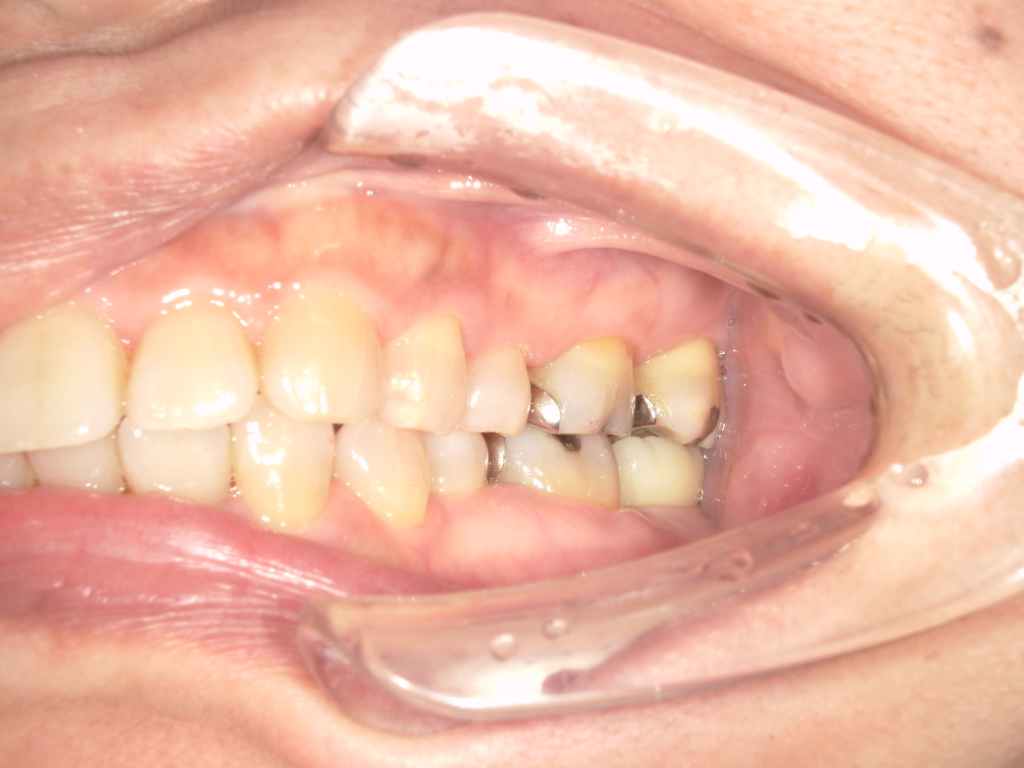

術前の写真は途中まで治療が進んでいまして、インプラントの仮歯が入っている状態です。

上の前歯4本をインプラントで治療しています。

被せものは全てセラミックスで治しています。